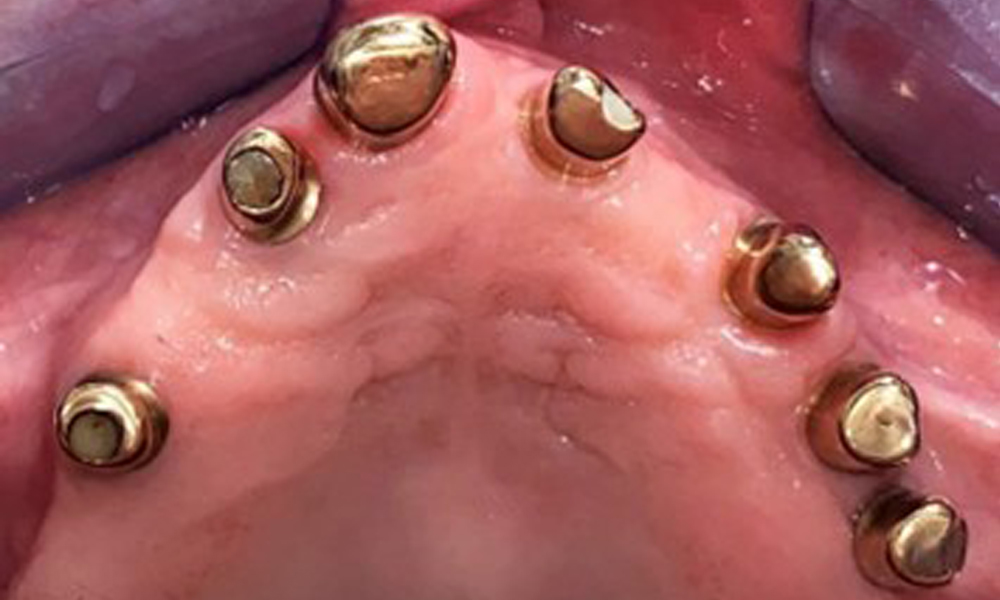

Occlusal view: Maxilla with removable, palateless denture.

Fig. 3: Occlusal view: Maxilla with removable, palateless denture.

The patient was fitted with a combined removable maxillary telescopic prosthesis more than 25 years ago (Fig. 1, Fig. 2, Fig. 3) and is very happy with her dentures. The patient has an adequate fixed denture for the mandible (Fig. 4).

The dental findings are as follows: Combined removable implant and tooth-supported telescopic prostheses on implants 15, 13, 21, 23, 24, 25 and tooth 11 (Fig. 1, Fig. 2, Fig. 3). The patient was fitted with a fixed mandibular denture. Adequate bridges were present over 37 to 34 and 45 to 47 (Fig. 4), the crown margins were intact and there were no active caries. A composite filling with a marginal gap was present on tooth 43. There was mandibular gingival recession, exposing 1 to 3 mm of root surface. This also applies to 11.